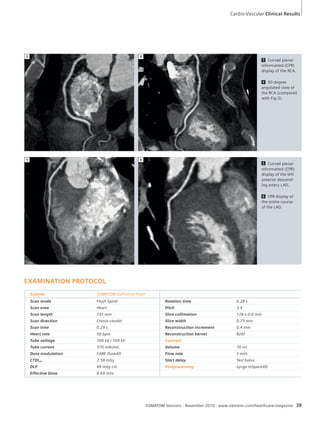

Cardio-Vascular

38 SOMATOM Definition Flash Ruling

out Coronary Artery Disease with

0.69 mSv